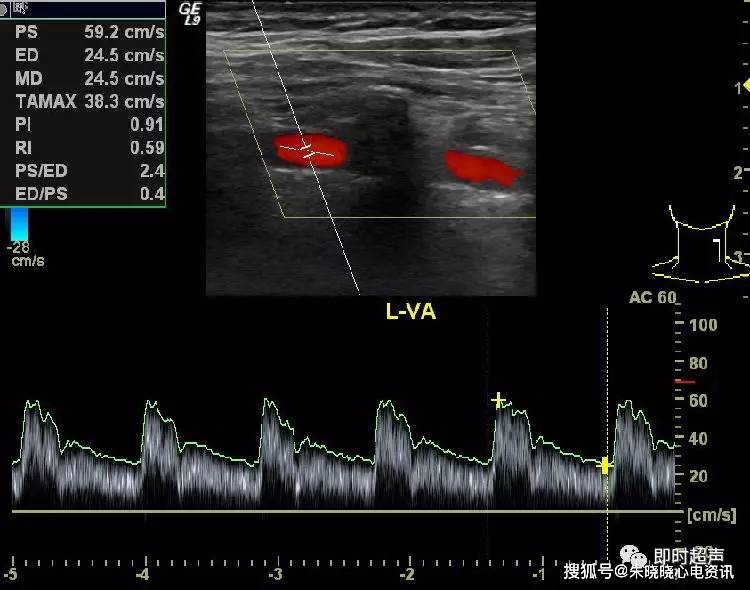

正常椎动脉彩色多普勒血流图彩色血流信号充盈于管腔内,其血流方向

图片尺寸750x590